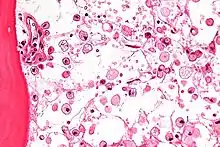

| Micrograph of Gaucher disease, with cells that have the characteristic crumpled tissue paper-like cytoplasm. H&E stain. | |